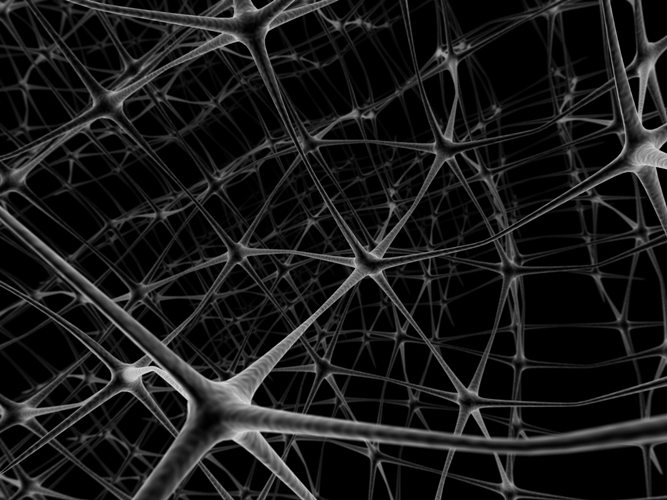

Nella malattia di Alzheimer i pazienti mostrano un inesorabile declino della memoria, che diventa sempre più grave con il decorso della malattia, accompagnato sia dalla morte delle cellule cerebrali, sia dalla formazione di placche e grovigli neuro fibrillari.